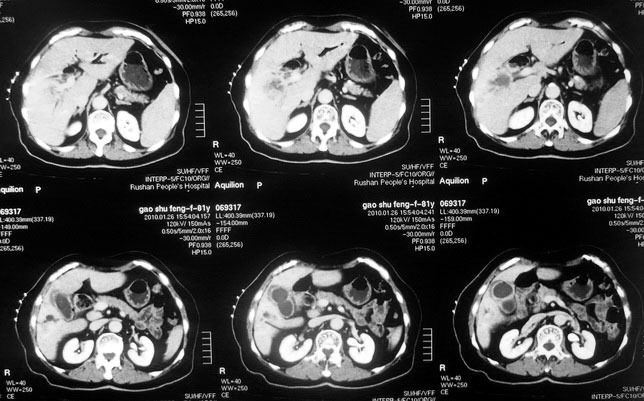

女,80岁既往有胆系手术史。近2月出现食欲不振,近20天出现畏寒发热,体重约下降10kg,体温一般在38℃左右。血常规wbc正常,中性比例88%,cea 10.3,afp、ca199均正常。做过一次肝穿,抽出约3ml仿佛脓性液体。这是她的增强ct扫描,请大家帮帮忙。另外想问问肝脓肿和胆管细胞癌的ct表现有什么区别。谢谢了。

【湘江一滴】化脓性胆囊炎及胆管炎,肝内胆管积气、积液、扩张;胆囊壁增厚、强化;胆周积液。未见肝内占位征象。

【sunbin】肝内见多个气体密度影伴气液面,胆囊壁增厚,胆囊周围低密度环绕,未见强化,支持化脓性胆管炎、胆囊炎。

最近复查ct,做了第二次穿刺抽脓,顺便做了涂片病理活检,结果找到恶性肿瘤细胞,诊断肝癌合并肝脓肿。看来大家都走眼了啊。